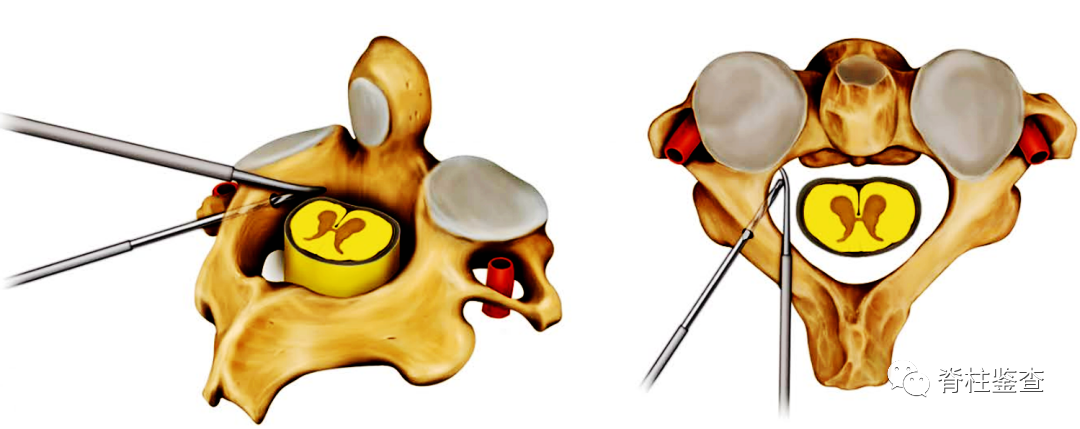

在C2峡部中点和C2椎板上缘处选择进钉点,磨钻开口后,用神经剥离子触诊椎弓根内侧缘,用手钻制作螺钉轨迹并故意穿破内侧皮质,螺钉轨迹比标准技术更偏内,保持螺钉轨迹在椎动脉沟( vertebral artery groove,VAG)和椎动脉(vertebral artery,VA)的内侧。通过直接观察峡部和剥离子的位置来指导螺钉内侧和头侧方向。

由于剥离子位于脊髓和椎弓根内侧之间,螺钉只会导致剥离子和脊髓内移,不会造成脊髓损伤,可安全地置入螺钉。确认螺钉轨迹位于剥离子内侧,椎弓根外侧皮质完好无损后,置入预定长度的螺钉。